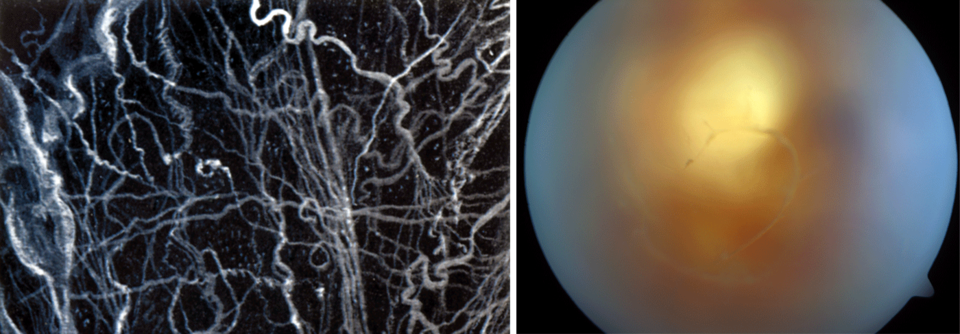

Mouches volantes – fliegende Mücken – nennen Augen­ärzte fast schon poetisch dieses Krankheitsbild. Was schon andeutet, dass meist nichts Ernstes dahintersteckt. Mit dem Fortschreiten der Lebensjahre trennen sich Kollagen und Hyaluronsäure voneinander, die zusammen mit Wasser das transparente Gel im Glaskörper des Auges bilden. Dies führt zu einer Aggregation und oft auch zur Verklumpung von Kollagenfibrillen, die dann von den Patienten meist als fadenförmige, fliegenähnliche oder an ein Spinnennetz erinnernde, semi­transparente graue Gebilde wahrgenommen werden.